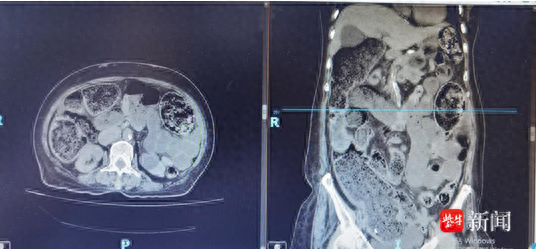

CT下显示肠道积气和积粪

肛肠科主任、主任医师王伟接诊后,详细了解了患者病史并查体,CT检查提示结肠、小肠梗阻,肠管内大量积粪,考虑是便秘引发的肠梗阻。此时陆奶奶的肠子已经“罢工”,无法自主排便,面对这种情况,王伟主任建议她住院治疗。